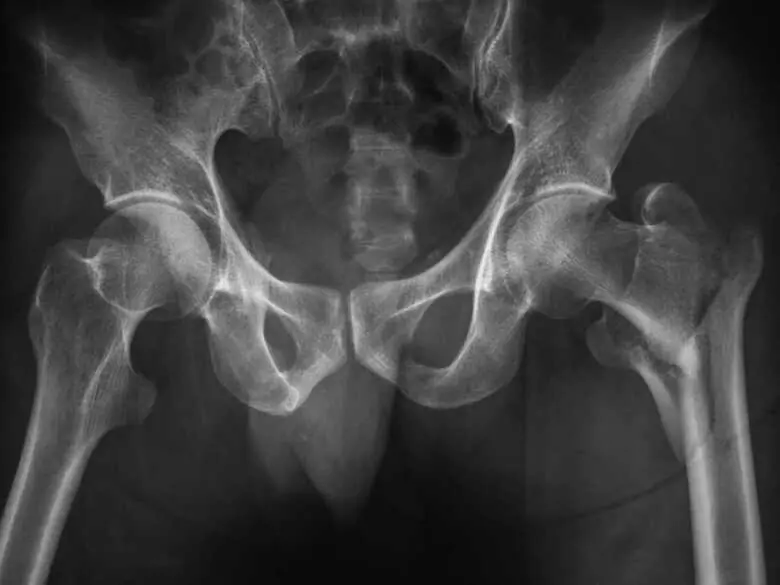

X-ray photo of hip